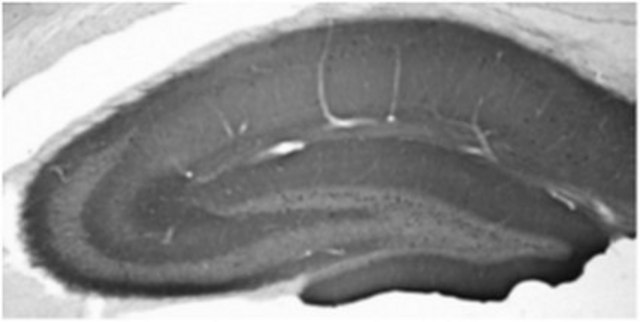

Immunohistochemistry Analysis: A representative lot detected GABA(B)R1 in adult rat hippocampus tissue (Prof. J. Trimmer, University of California, Davis).